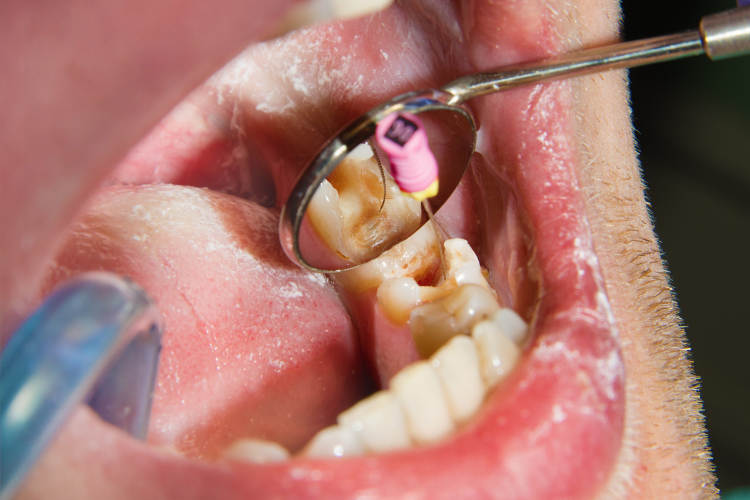

The root canals are irrigated with a disinfectant solution to remove any remaining debris and bacteria.

The dentist or oral surgeon will make an incision in the gum tissue to access the tooth and bone Rest and avoid strenuous activities for a day or two..